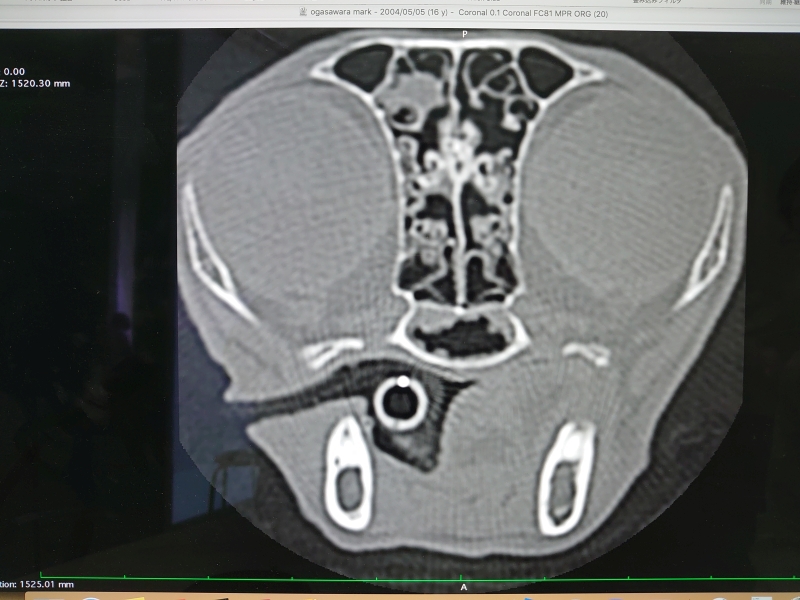

先生からCTと内視鏡の映像を見せてもらった

確かに先日見せてもらったワンちゃんの狭窄とは異なり、空洞は広いようだけど何かがへばりついてる..